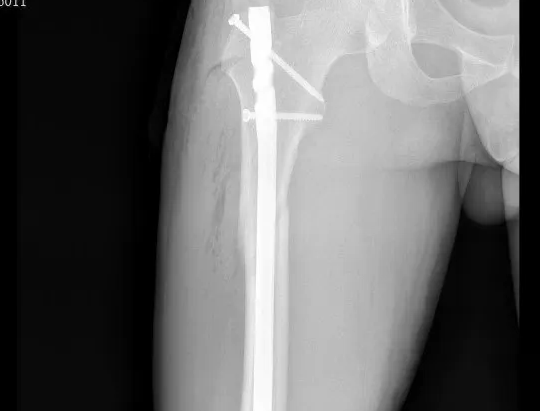

“叮铃铃……”急诊科来电:“马上接收一名车祸伤患者,男性,31岁,右侧髋部损伤!”接到通知后,我院骨科医护团队迅速响应,第一时间完成伤情查体。只见患者右髋及股骨区域肿胀明显、严重畸形...